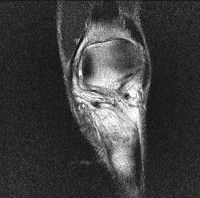

무릎 mri 간단히 봐주실 수 있으시나요 ㅠㅠ

안녕하세요 8년전 십자인대 수술하고 최근 무리한 운동에 무릎 불편감이 생겨서

mri 찍었습니다.

진단결과는 첫 찍은 병원에서 활액막염 이라는 진단을 받았습니다. 혹시 봐주실 수 있으실까요?

올라온 MRI가 단편적이라서 정확한 진단에 어려움이 있지만 십자인대에는 큰 이상이 있지는 않은것 같으며, 무릎관절내 물이 있는 것으로 보아 활액막염의 진단이 맞을 것 같습니다.

하지만 단편적인 영상이기 때문에 촬영병원에서 정확한 판독지 등을 받으시는 것이 좋겠습니다.